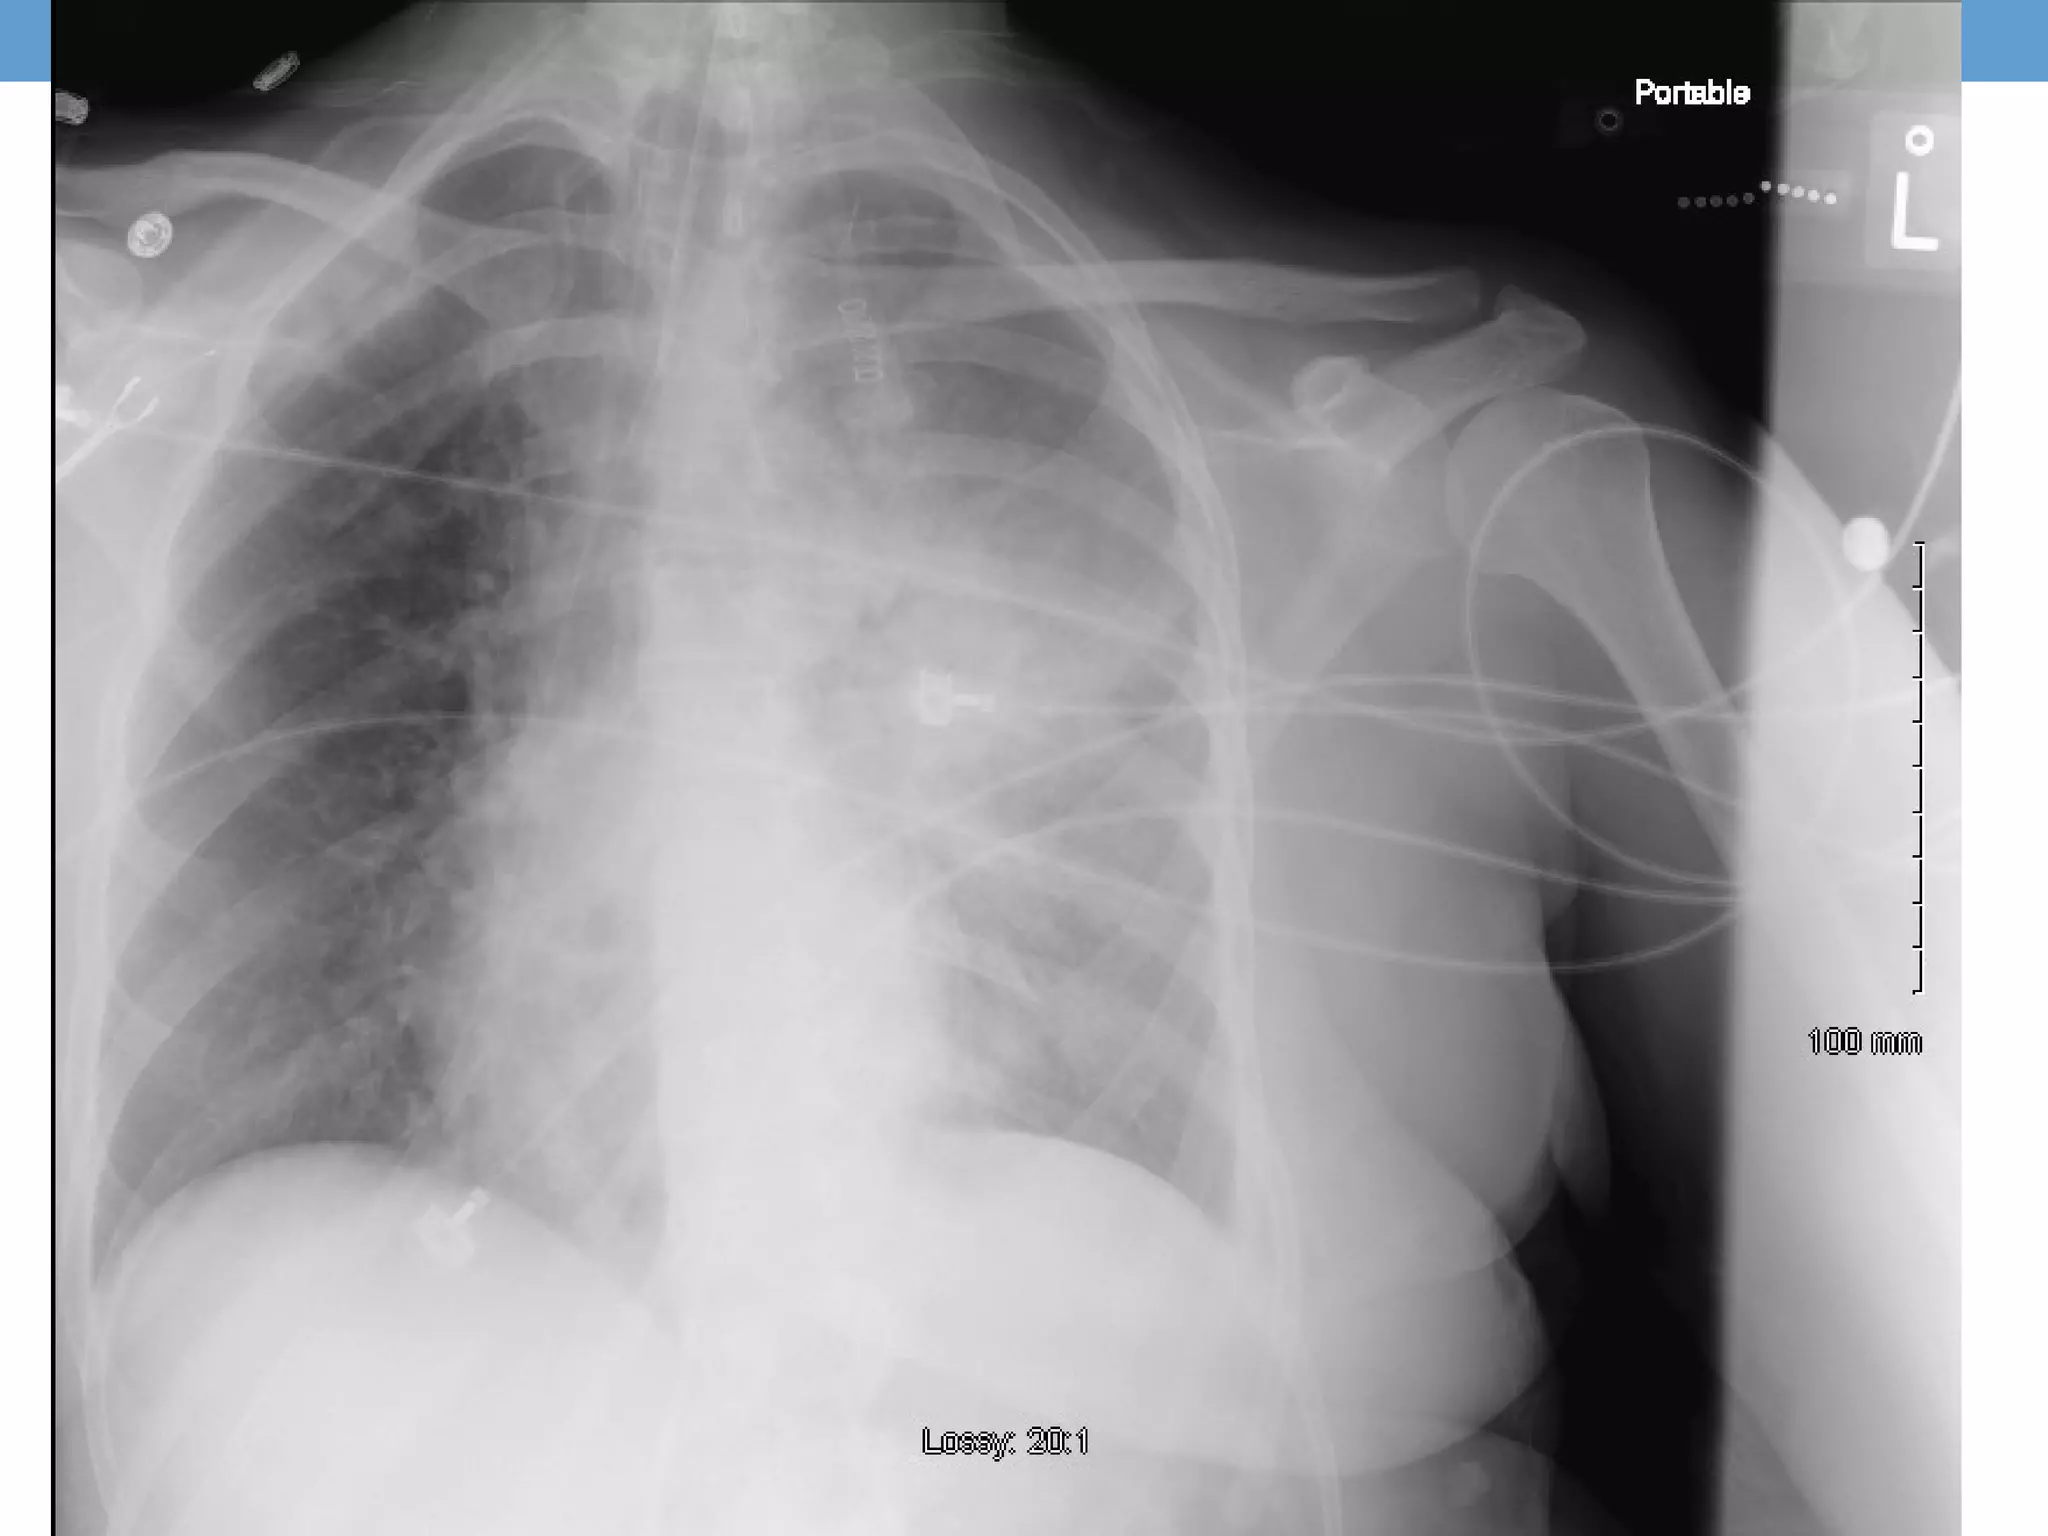

Day of Hospitalization #2

• 7.38 / 30 / 60 / 18 on 0.55 (PaO2:FiO2 109) [05:00, Day 2]

• Systolic pressure continued to drop despite 4L IVf

78/46, 138, 33, 98% on 0.60

The patient was declining despite aggressive supportive

care.

• Bedside Echocardiogram was performed suggesting RV

ballooning with septal flattening

• A STAT CT PE protocol of chest was obtained

• A STAT echocardiogram was obtained

Day of Hospitalization#2 • 7.38 / 30 / 60 / 18 on 0.55 (PaO2:FiO2 109) [05:00, Day 2] • Improving mental status, responding to commands but… • Systolic pressure continued to drop despite 4L IVf 78/46, 138, 33, 98% on 0.60 • Levophederine gtt started The patient was declining despite aggressive supportive care.

Day of Hospitalization#2 • Bedside Echocardiogram was performed suggesting RV ballooning with septal flattening • A STAT CT PE protocol of chest was obtained • A STAT echocardiogram was obtained